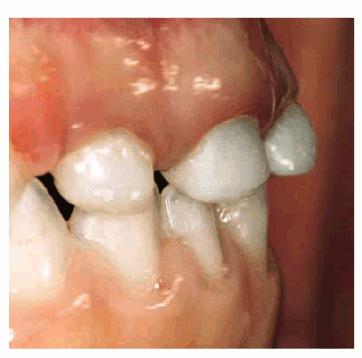

A male patient, 3 years, 9 months old.

PROBLEM: The patient presented with rampant caries, loss of the anterior

teeth, and advanced caries in the posterior teeth (Figure 27-4A

Figure 27-4A: A patient of 3 years, 9 months, with rampant caries and loss of an anterior tooth.

TREATMENT: The root of G is extracted, and the posterior teeth are

restored with composite resins. An attempt to maintain pulp vitality is made by

placing calcium hydroxide on the pulp. A pedodontic prosthesis has been used to

maintain the anterior space, preserve the vertical dimension, improve alveolar

growth, and avoid supereruption of the lower anterior teeth (Figures 27-4B to

D

Figure 27-4B to D: The posterior teeth are restored with composite resin, and a pedodontic prosthesis is placed.

RESULT: Good function is restored, and the desired psychological result has been achieved, with lasting benefits. The patient has undergone periodic yearly visits: teeth #3 and #14 have erupted (Figures 27-4E and F

Figure 27-4E and F: Proper function is reached and the desired psychological result has been achieved in the long-term follow-up. Note that teeth #3 and #14 have erupted.